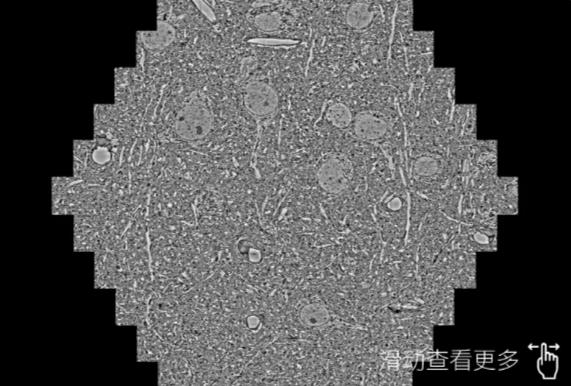

鼠脑切片。左图使用天津蔡司天津扫描电镜MultiSEM706对165μmx143pm面积区域成像,耗时仅需1.5秒。右图为鼠脑切片中30μm区域放大效果。样品由芝加哥大学B.Kasthuri提供。